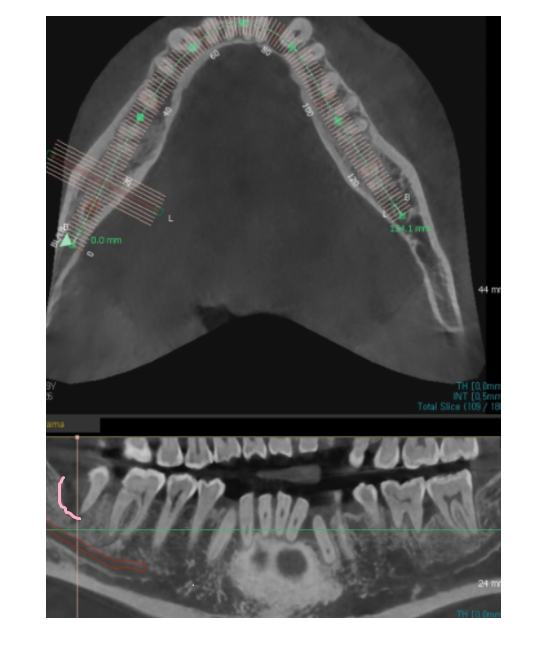

ct 상에서 잇몸 뼈 한쪽이

움푹 패여졌네요.

잇몸 뼈 깊이를 재어보니 12.8mm 정도 나왔습니다.